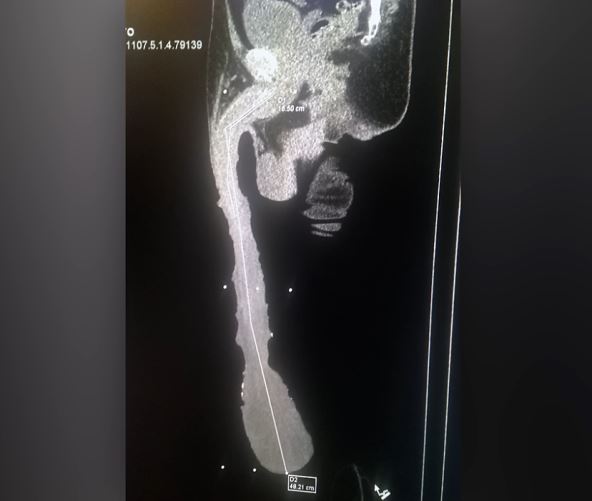

Medicinski pregledi i ultrazvuk potvrdili su da je njegov penis stvaran, iako neki stručnjaci tvrde da je stvarna dužina oko 15 cm, dok je ostatak samo višak kože. Kabrera je odbio operaciju i sanja o tome da njegov penis bude zabeležen u Ginisovoj knjizi rekorda.